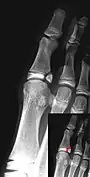

Additional images